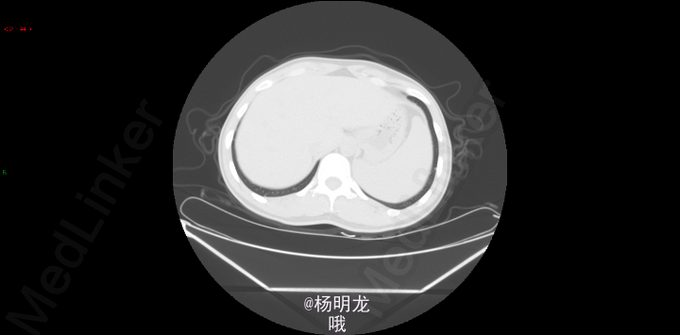

术前诊断 直肠癌 升结肠癌术后 双肺多发结节 转移瘤? 名称:开腹直肠癌切除,结肠造口术(Hartmann术) 探查:右上腹粘连,肝脏只探及部分,质地略韧,未触及肿物。直肠肿物上端位于盆底腹膜返折处,侵及腹膜,与左侧精囊粘连紧密。肿瘤4x4x3cm。无腹水,右腹部原术区未触及异常。 由于盆腔狭窄、粘连,向深部游离骶前间隙时出现静脉出血,紧急压迫止血。通过压迫不再出血后,于肿瘤上缘15 cm切断乙状结肠,于肿瘤下缘3cm以闭合器闭合直肠并切断直肠,切除肿瘤和肠管。 发生骶前静脉大出血,估计有2000ml。输血红细胞4u,血浆4u。

“结肠癌术后,化疗后” (1)(直肠切除标本) 直肠中-低分化腺癌,部分呈微乳头结构,伴少许黏液分泌,局部伴坏死,可见脉管瘤栓及神经侵犯。肿瘤细胞退变,伴纤维组织增生,符合中度治疗后改变(TRG3级),肿瘤侵透肌层累及直肠旁脂肪及盆底腹膜及环周切缘。上切缘及下切缘均未见癌。 淋巴结转移性癌(5/32) 肠壁淋巴结 5/15 肠系膜淋巴结 0/17 ypTNM分期:ypT3N2a 病例特点: 1.青年男性,双原发大肠癌; 2.升结肠癌(pTxN1bM1) 3.直肠癌(ypT4N2aMx),脉管瘤栓、神经侵犯,环周切缘受累。